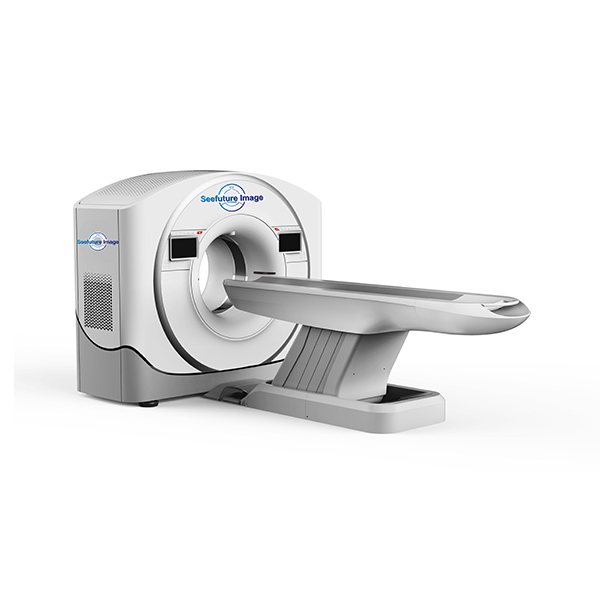

OCEAN 128S CT

OCEAN 128S CT (128-slice)

Precision in Every Step

Precision in Every Day

Prioritize dose care to enhance the scanning experience

25 MHU LMB tube, empowered reliability, efficiency, and longevity

Sky-eye and Eagle-eye elevate precision with streamlined workflow

0.33 s rotation speed and 40mm detector take cardiac imaging to new heights.

Key Data:

| Rotation time | 0.33 s/360° |

| Tube heat capacity | 8.0 MHU(Eff. 25 MHU) |

| Generator power | 80 kW |

| kV steps | 70, 80, 100, 120, 140 kV |

| mA range | 5 – 667 mA |

| Slices | 128 slices |

| Aperture bore | 72 cm |

| Spatial resolution | 21.0 lp/cm@0%MTF |

| Sky-eye | Optional |